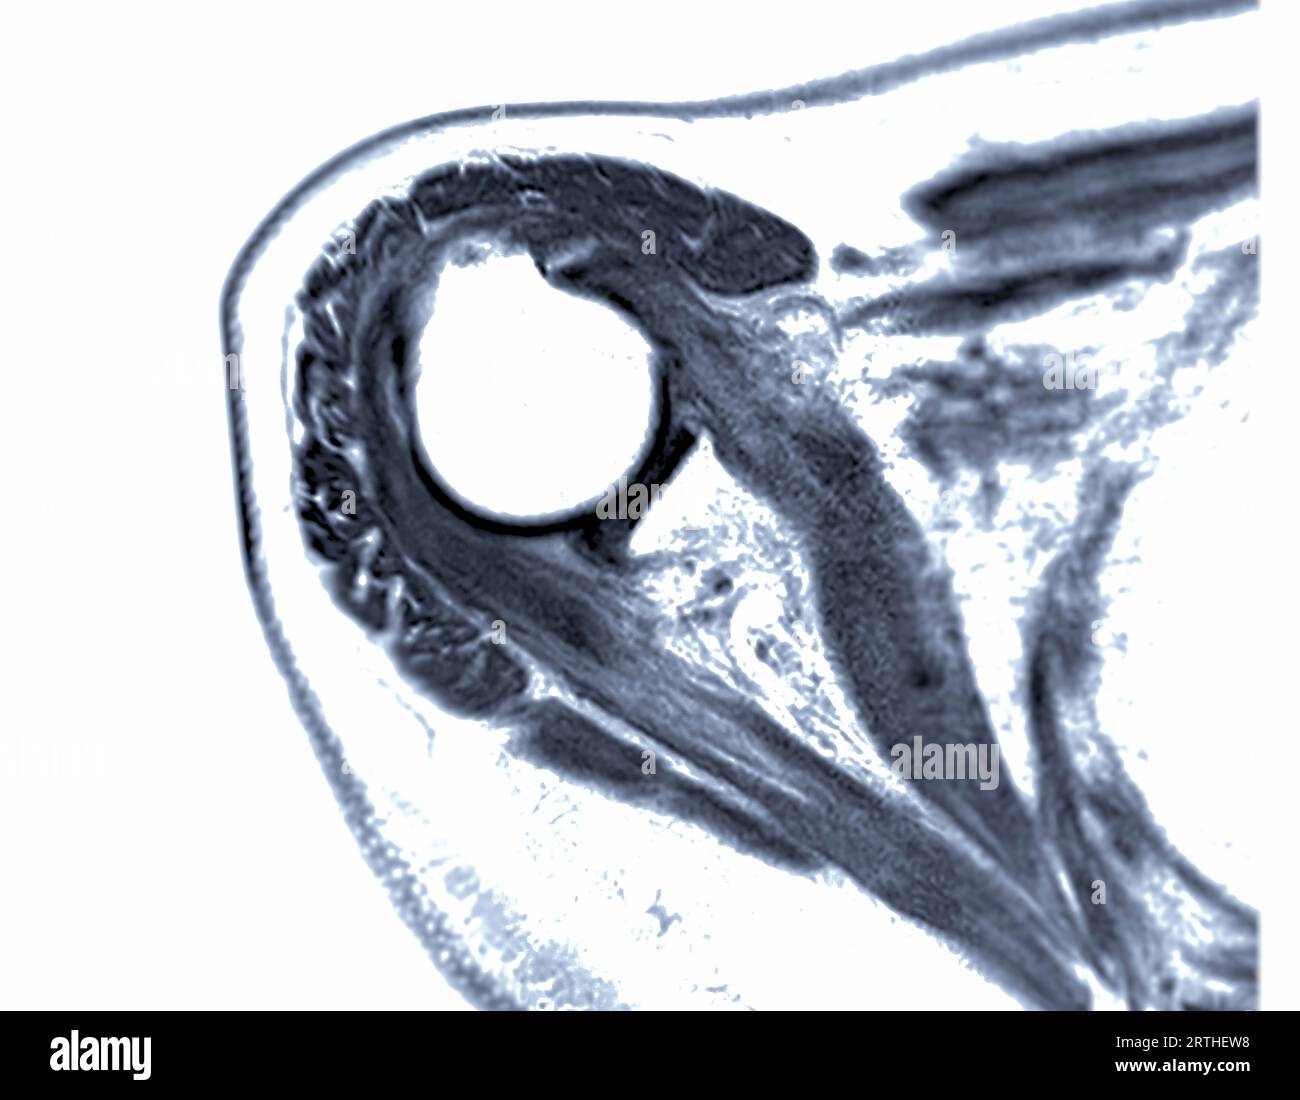

MRI Shoulder Musculoskeletal Imaging

MRI Shoulder Musculoskeletal Imaging What Can Mri Of Shoulder Detect in particular, the images include your muscles, ligaments, and cartilage as well as any other components. the evaluation of the shoulder, and especially its soft tissue structures, is best done with an mri. magnetic resonance imaging (mri) of the shoulder uses a powerful magnetic field, radio waves and a computer to produce. magnetic resonance imaging (mri). What Can Mri Of Shoulder Detect.